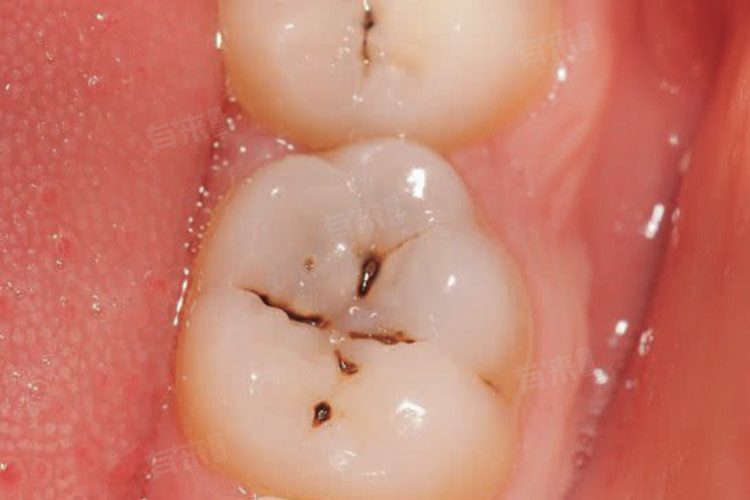

3、临床症状:大多不会有明显的不适症状,釉质在早期可能呈现出褐色、黑褐色的表面粗糙的斑点、斑块。随着龋坏的持续发展,会逐渐造成牙齿表面的破坏。

3、临床症状:会有明显的龋洞形成,通常为黄色或者黑色。牙本质由于矿物质脱离、有机物质溶解而发生软化,同时受食物色素侵蚀,牙本质会发生颜色变化,一般会变为黄褐色。牙齿会对冷、热、酸、甜等食物异常敏感,但通常在刺激消失后,症状会有所缓解。